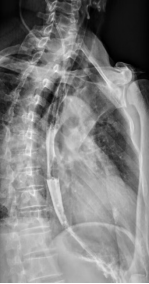

该研究中的患者彭先生因“发现食管气管瘘20余天”到我院治疗。彭先生两年出现反复咳嗽、咳黄脓痰,当地医院就诊后诊断为“肺脓肿”,予抗感染对症治疗后,黄脓痰转向白痰,20余天前彭先生出现咳血,遂至外院查胸部CT,结果提示:食管-右肺下叶背段纵隔旁支气管瘘。

彭先生到我院心胸外科完善相关检查,明确诊断,排除手术禁忌后行单孔胸腔镜下食管气管瘘修补术,手术时间3小时。术后1周复查造影,未见造影剂外漏。术后9天彭先生就开始进口进食了。术后11天康复出院。

术后复查未见造影剂外渗